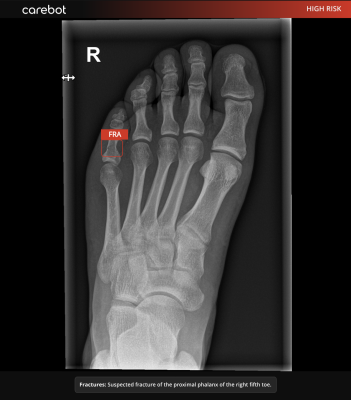

When the system identifies a lesion on a musculoskeletal X-ray, the LLM instantly drafts a one-sentence, localization-aware finding, for example: “Suspected fracture of the proximal phalanx of the right fifth toe.”

The text is pushed directly into the hospital information system (HIS); the radiologist reviews, adjusts if necessary, and signs off—no window-switching, no prompts, no re-typing. “At Carebot, we believe radiologists shouldn’t have to ‘chat’ with AI—they should get structured, clinically relevant output delivered right into their workflow. That’s why we’re now working towards integrating large language models (LLMs) to enhance our musculoskeletal (MSK) AI solution, Carebot AI Bones,” says Daniel Kvak, CEO of Carebot and adds: “We’re not building a chatbot—we’re building a clinically validated tool that delivers localization-aware, natural-language findings into the HIS in real time. Our goal is to make this the first MDR-certified radiology AI solution powered by an LLM.”